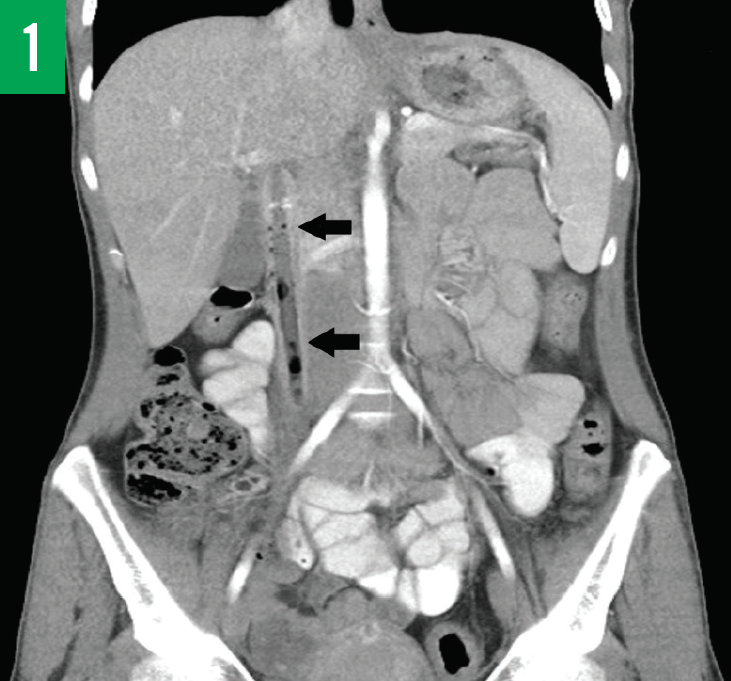

A 7-year-old previously healthy and active boy without comorbidities presented to the pulmonary clinic with a 6-month history of dry cough, recurrent left lower lobe pneumonia, and limited physical...